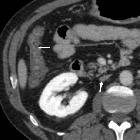

Hypovolemic

shock with subtle imaging signs: systemic capillary leak syndrome. Most of the collapsed colon showed diffuse, moderate circumferential mural thickening (thin arrows) with mucosal enhancement and mural hypoattenuation suggesting submucosal oedema.

shock with subtle imaging signs: systemic capillary leak syndrome. Diffuse, moderate circumferential mural thickening (thin arrows) with mucosal enhancement and mural hypoattenuation suggesting submucosal oedema. Note marked nephrogram, slit-like inferior vena cava (arrow).